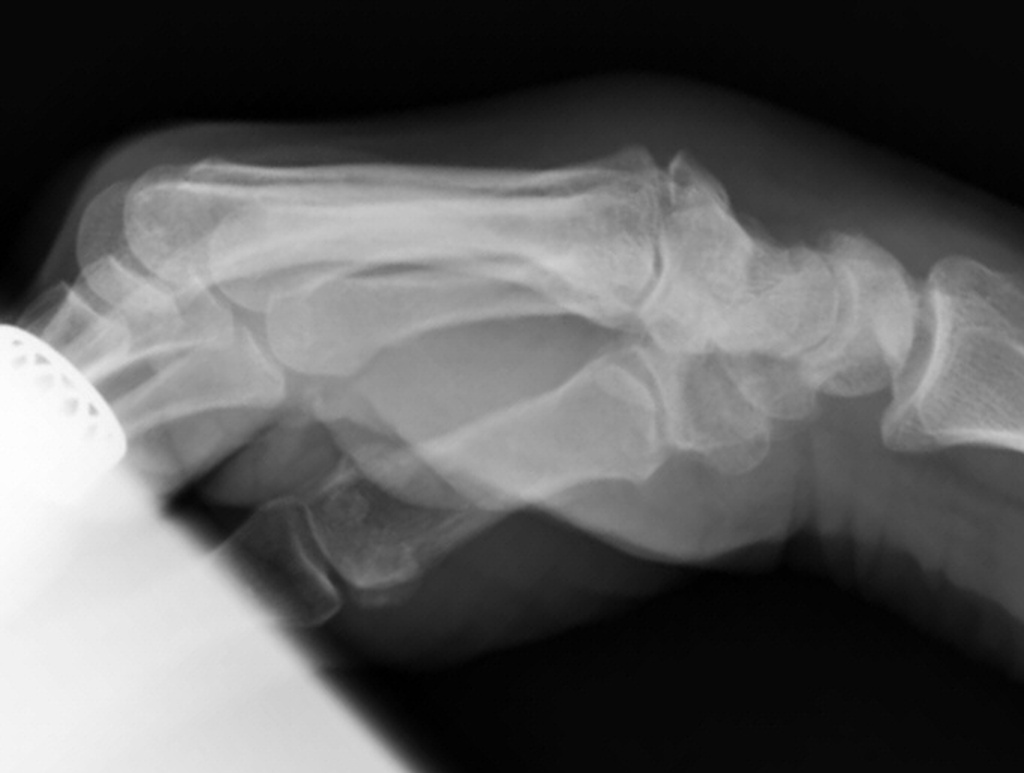

Lateral clenched fist xray tangential view profiles the prominence, here with an exostosis of the metacarpal base.